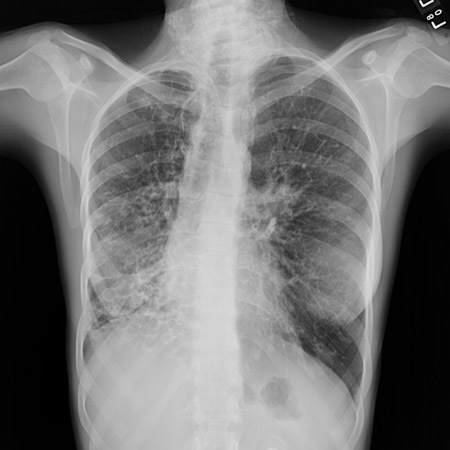

What would you see on a CXR/CT of bronchiectasis?

(CXR with lack of normal tapering producing a tram line below)

CXR - obscured hemidiaphragm, thin-walled ring shadows with or without fluid levels, tram lines (sign of thickened tapered walls of bronchiectasis), tubular or ovoid opacities

CT - thickened, dilated airways with or without air fluid levels; varicose constrictions along airways; cysts and/or tree-in-bud pattern